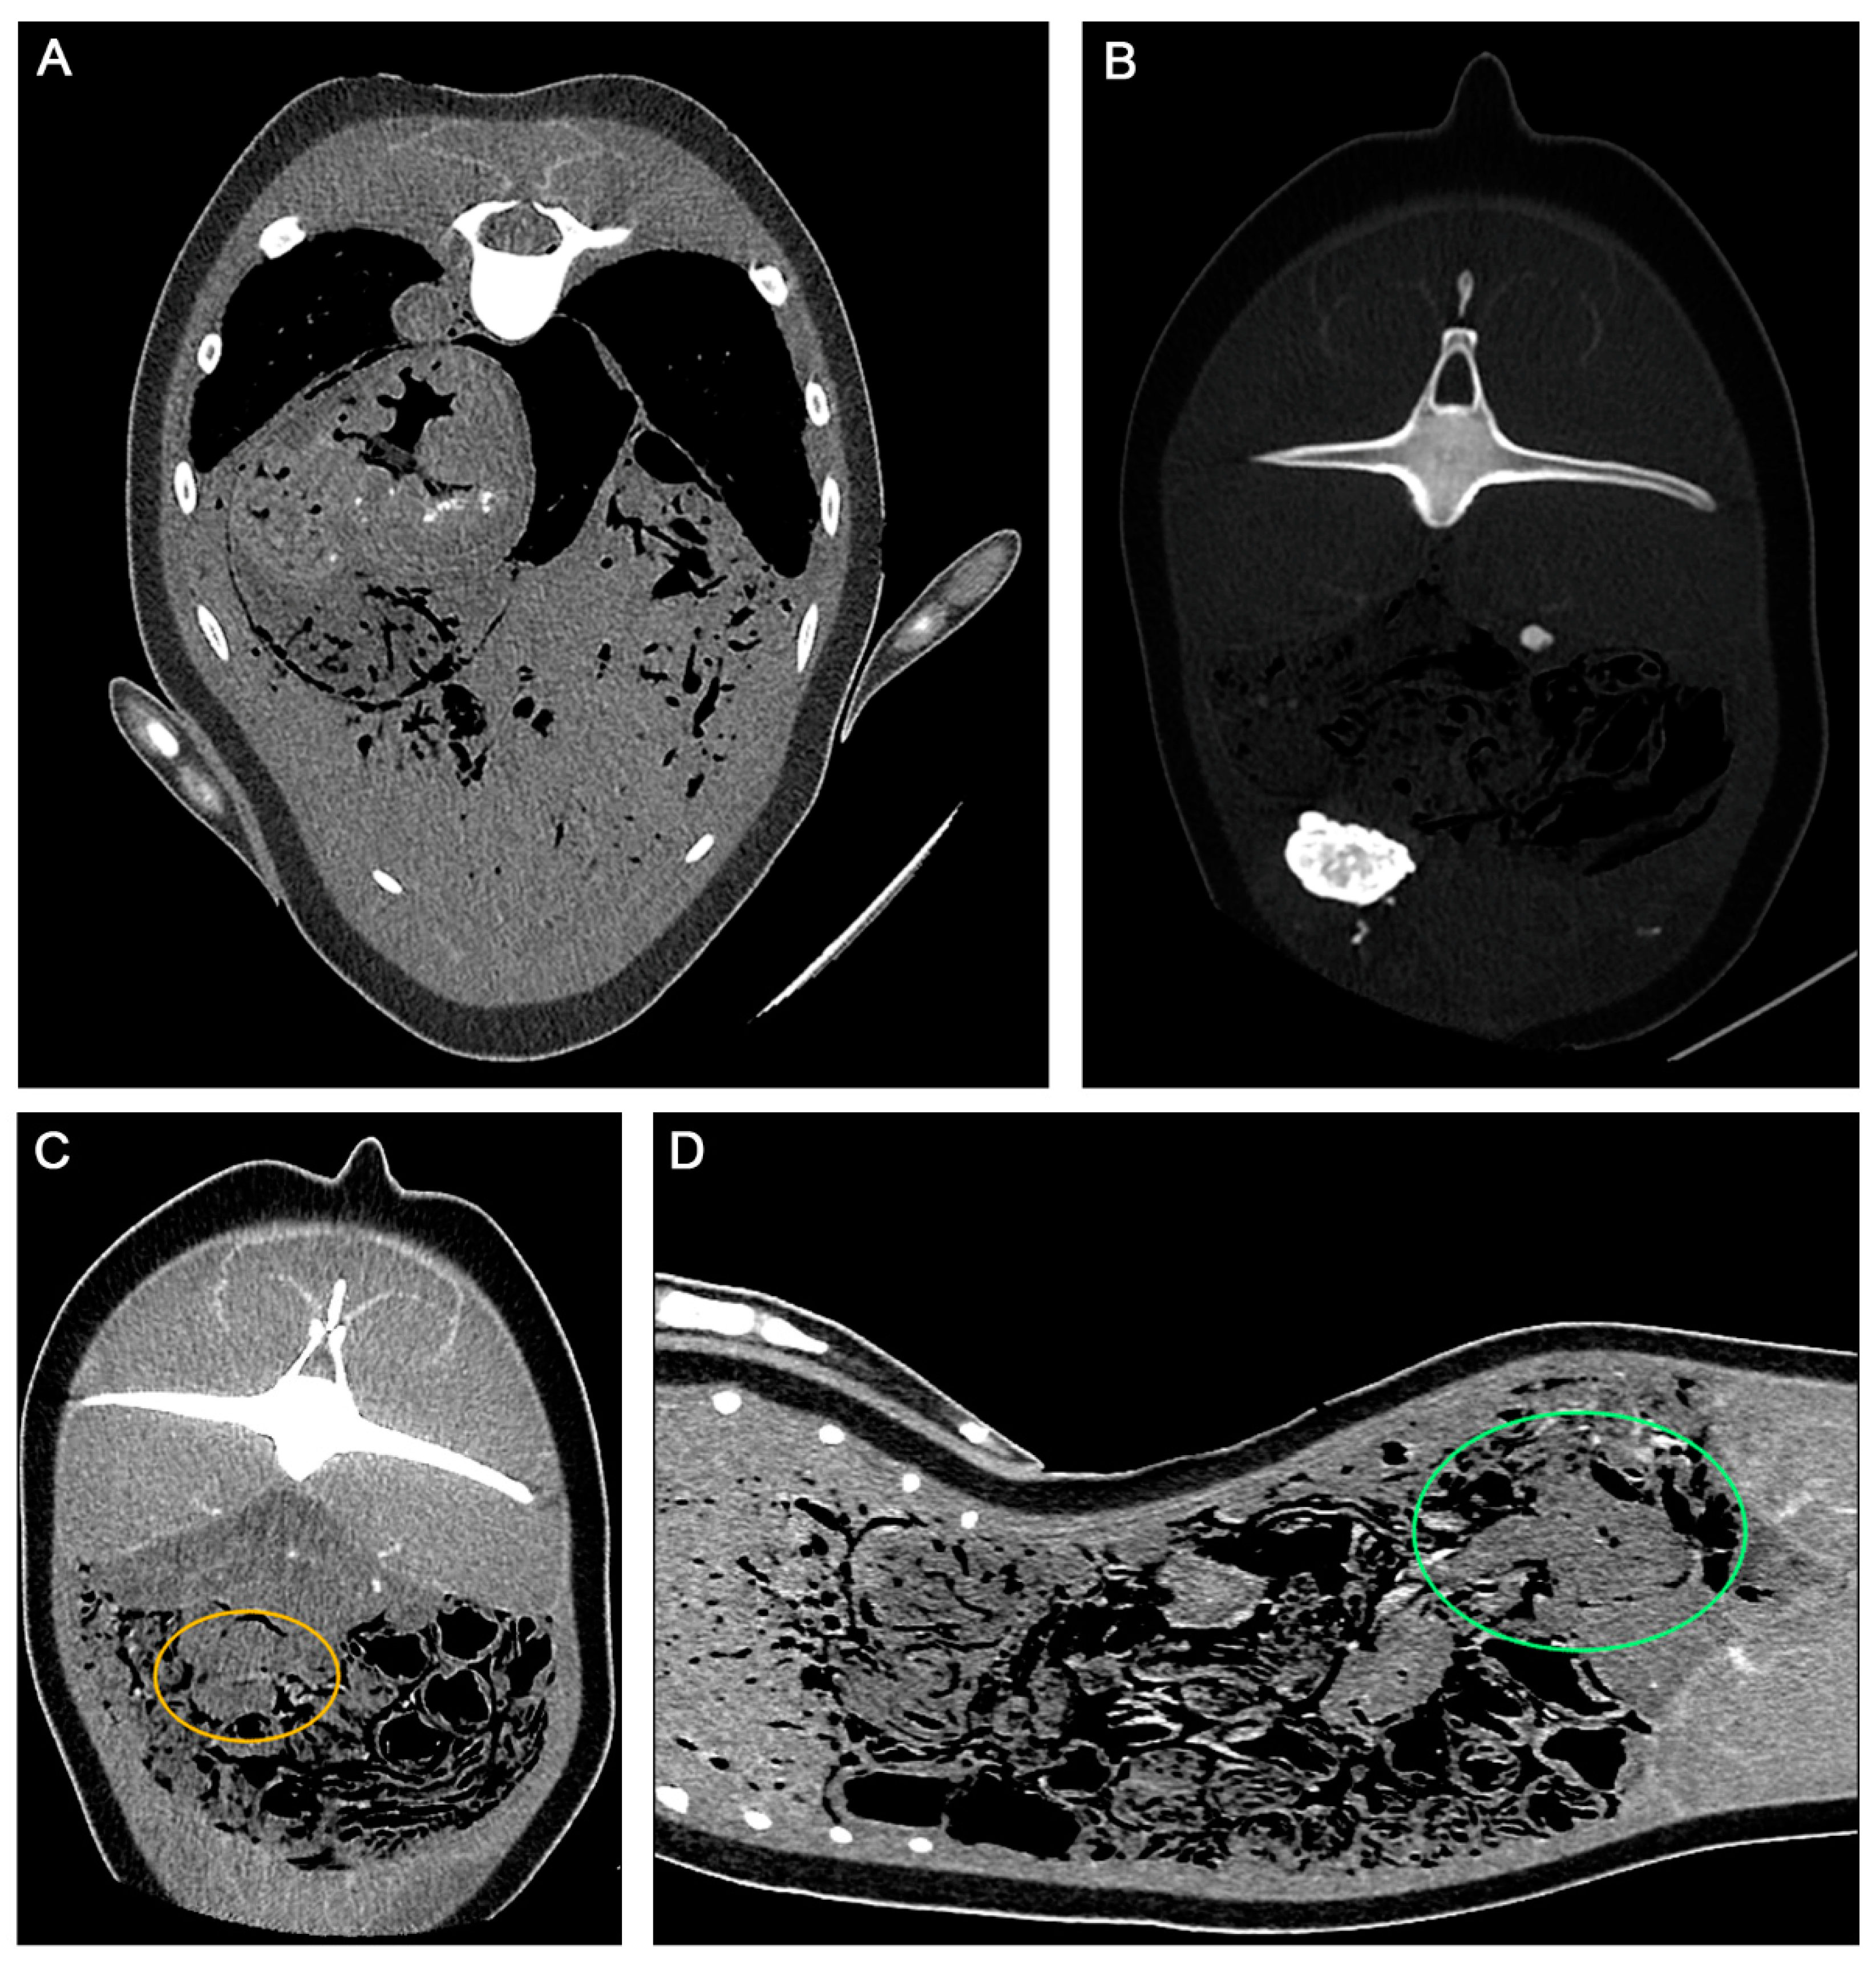

- Yuen, A.H.L.; Kim, S.W.; Lee, S.B.; Lee, S.; Lee, Y.R.; Kim, S.M.; Poon, C.T.C.; Kwon, J.; Jung, W.J.; Giri, S.S.; et al. Radiological investigation of gas embolism in the East Asian finless porpoise (Neophocaena asiaeorientalis sunameri). Front. Mar. Sci. 2022, 9, 711174. [Google Scholar] [CrossRef]

- Yuen, A.H.L.; Lee, S.B.; Kim, S.W.; Lee, Y.M.; Kim, D.G.; Poon, C.T.C.; Seo, J.-P.; Baeck, G.W.; Kim, B.Y.; Park, S.C. Fatal upper aerodigestive tract obstruction in an East Asian finless porpoise (Neophocaena asiaeorientalis sunameri): Findings in post-mortem computed tomography. Forensic Sci. Med. Pathol. 2023, 19, 1–8. [Google Scholar] [CrossRef]

- Gopireddy, D.R.; Soule, E.; Arif-Tiwari, H.; Sharma, S.; Kanmaniraja, D.; Jain, K.; Lall, C. Spectrum of CT findings related to bowel adhesions without bowel obstruction: A comprehensive imaging review. J. Clin. Imaging Sci. 2020, 10, 80. [Google Scholar] [CrossRef] [PubMed]